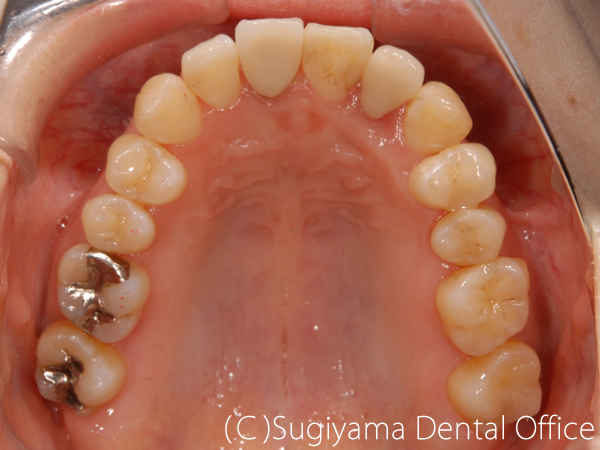

前歯を綺麗にしてほしいということで来院した女性の患者さんです。

親知らずは抜歯しましたが、そのほかは1本も歯を抜かずに矯正治療を仕上げました。

変色が著しかった前歯2本はオールセラミッククラウンで治しました。

歯が綺麗になったことで、笑顔がさらに美しくなりました。